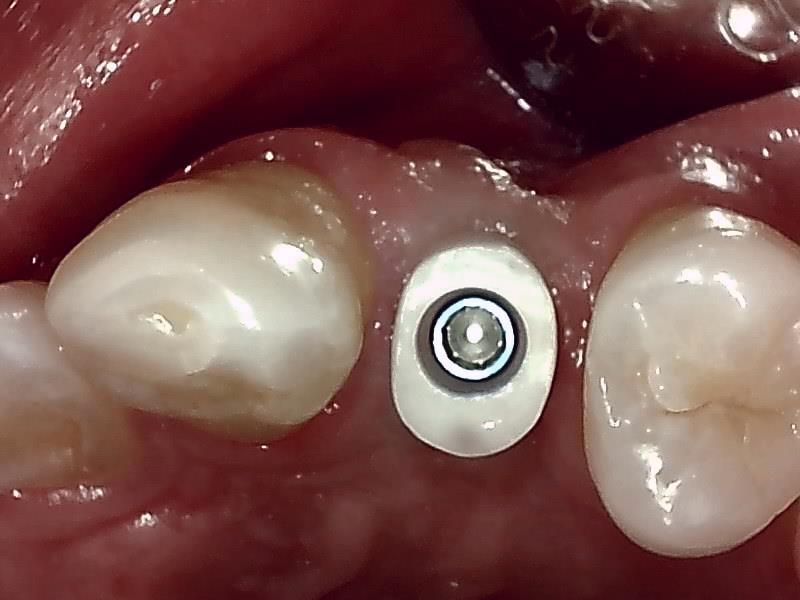

アバットメント装着 (左上)

(ジルコニアアバットメント)

歯肉の整形 (左上)とても綺麗な良い歯肉の状態です。